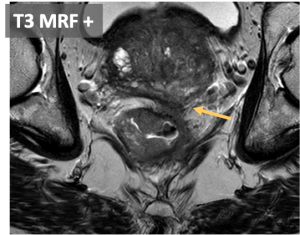

- T3: Tumor extension into the mesorectal fat, beyond muscularis propia. T3 can be subclassified according to the extramural invasion depth:

- Involvement of the mesorectal fascia (MRF+) is a associated with higher risk of local recurrence.